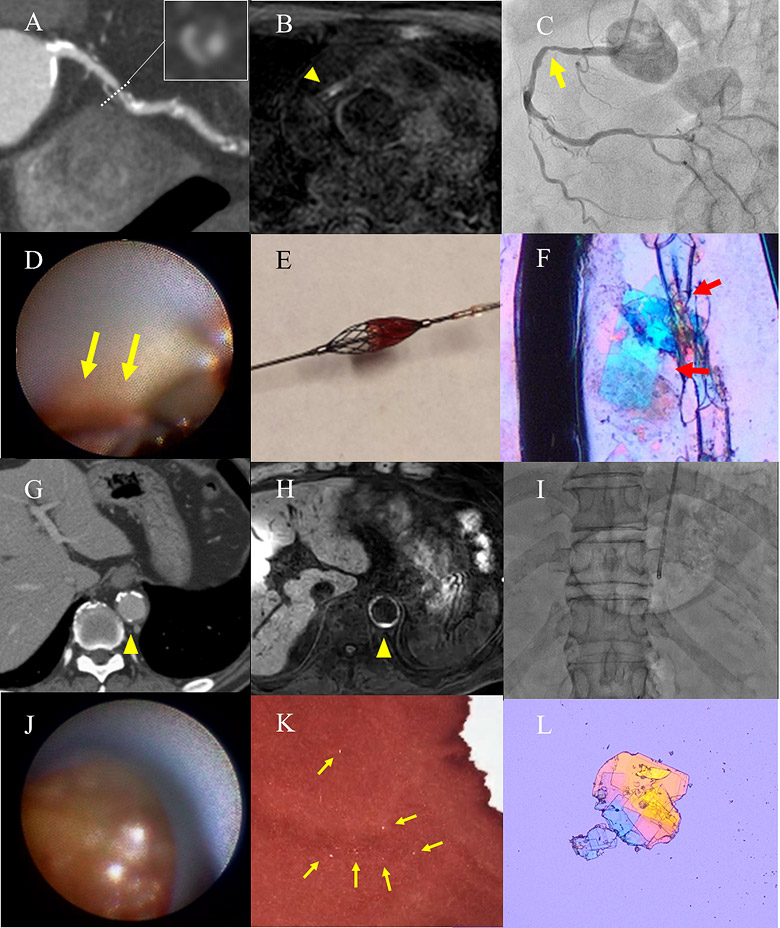

裁断済 knack & pitfalls 冠動脈外科の要点と盲点 第2版。渡部浩明先生が下行大動脈および冠動脈プラークから。主訴から攻める心電図〜異常波形を予測し、緊急症例の診断に迫る。「冠動脈外科の要点と盲点 第二版」高本眞一 / 坂田隆造価格 ¥ 19,800(税込み)#高本眞一 #坂田隆造 #本 #BOOK #健康 #医学こちらの商品は“裁断済み”です。二十世紀の疫病―低血糖症―心身を蝕む恐るべき食原病。中に書き込みはありません。失語症者の実用コミュニケーション 臨床ガイド。裁断済の意味がわからない方はご遠慮下さい。看護学校教科書。発送方法は佐川急便/日本郵便を選択しています。All About 開放隅角緑内障(裁断済み)。値下げの予定はありません。タッチフォーヘルステキスト中国語版。インテグラル・ワークフローが心臓解析を変える-技術解説。表面にスレがあり多少使用感があり。本上下に名前の押印あり、消した跡と汚れが軽度あります(写真参照)。PCIマル秘裏技テクニック。ナーシング・キャンバス クリニカルスタディ。”裁断済み“とは、書籍の綴じている側を切り、ページ全部がバラバラになった状態です。裁断済みの為、“全体的に状態が悪い\"としております。インテリアコーディネーター1次試験対策 過去問題、予想問題、試験対策問題集4点。胃の手術 改訂第2版 榊原宣著 永井書店。中古品にご理解ある方のみご購入お願いいたします。キャンセル・返品はお受けできませんので、 ご確認よろしくお願いします。これでわかる 薬用植物 中田福市, 中田貴久子 、新星図書出版 健康 長寿 知恵。「最新 医学大辞典 第3版」。匿名の取引となりますが、到着まで数日間要します。ご理解いただいた上での購入お願いします。国試対策 看護 クリニカルスタディ2016.4〜2017.3。上田 敏リハビリテーション基礎医学 医学書院。ご了承ください。